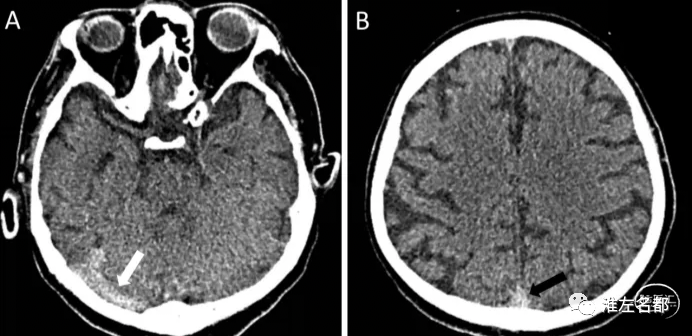

急性早期的脑静脉窦血栓在CT呈明显高密度改变。CT横断面扫描图像上,横窦、乙状窦、直窦急性血栓可表现为高密度“条索征”(Cord Sign),上矢状窦血栓表现为上矢状窦后部的高密度“三角征”(Delta Sign)。亚急性和慢性静脉窦血栓,CT平扫均呈等密度。

右侧横窦(图A,白箭)和上矢状窦(图B,黑箭)

急性血栓高密度征。